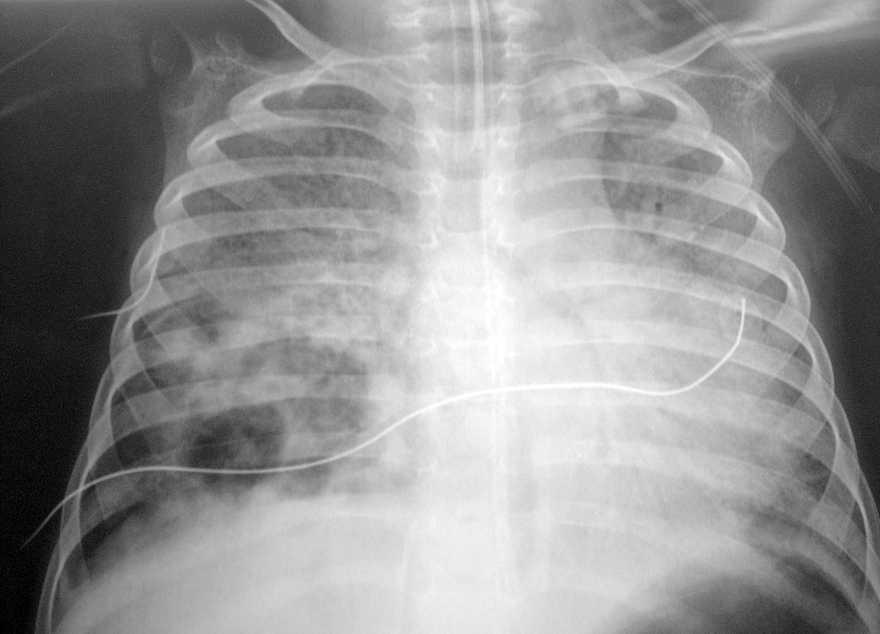

El paciente presentaba una coagulopatía que requirió tratamiento con plasma fresco congelado y vitamina K, así como anemia de 8 g/dl de hemoglobina (Hg) que requirió transfusión de concentrados de hematíes. La función respiratoria fue empeorando progresivamente, presentando presiones altas en la vía aérea (pico de 45-50 cm H2O, meseta de 19 cm H2O, compliance dinámica de 3,4 ml/cm de H2O y estática de 12 ml/cm H2O). Se asoció NO2 hasta 30 ppm al tratamiento. Tras aumentar progresivamente la presión positiva al final de la espiración (PEEP) hasta 7 cm H2O, el pulmón derecho aparecía más aireado, y tras la resolución del componente atelectásico que estaba asociado a la neumonía (fig. 1) se apreciaron dos imágenes compatibles con abscesos o bullas en el pulmón derecho (fig. 2). La evolución posterior fue hacia un síndrome de distrés respiratorio agudo (fig. 3). Se inició tratamiento con ventilación de alta frecuencia con una mejoría inicial de la oxigenación que no se mantuvo posteriormente.

Figura 1. Atelectasia asociada a neumonía basal y media derecha.